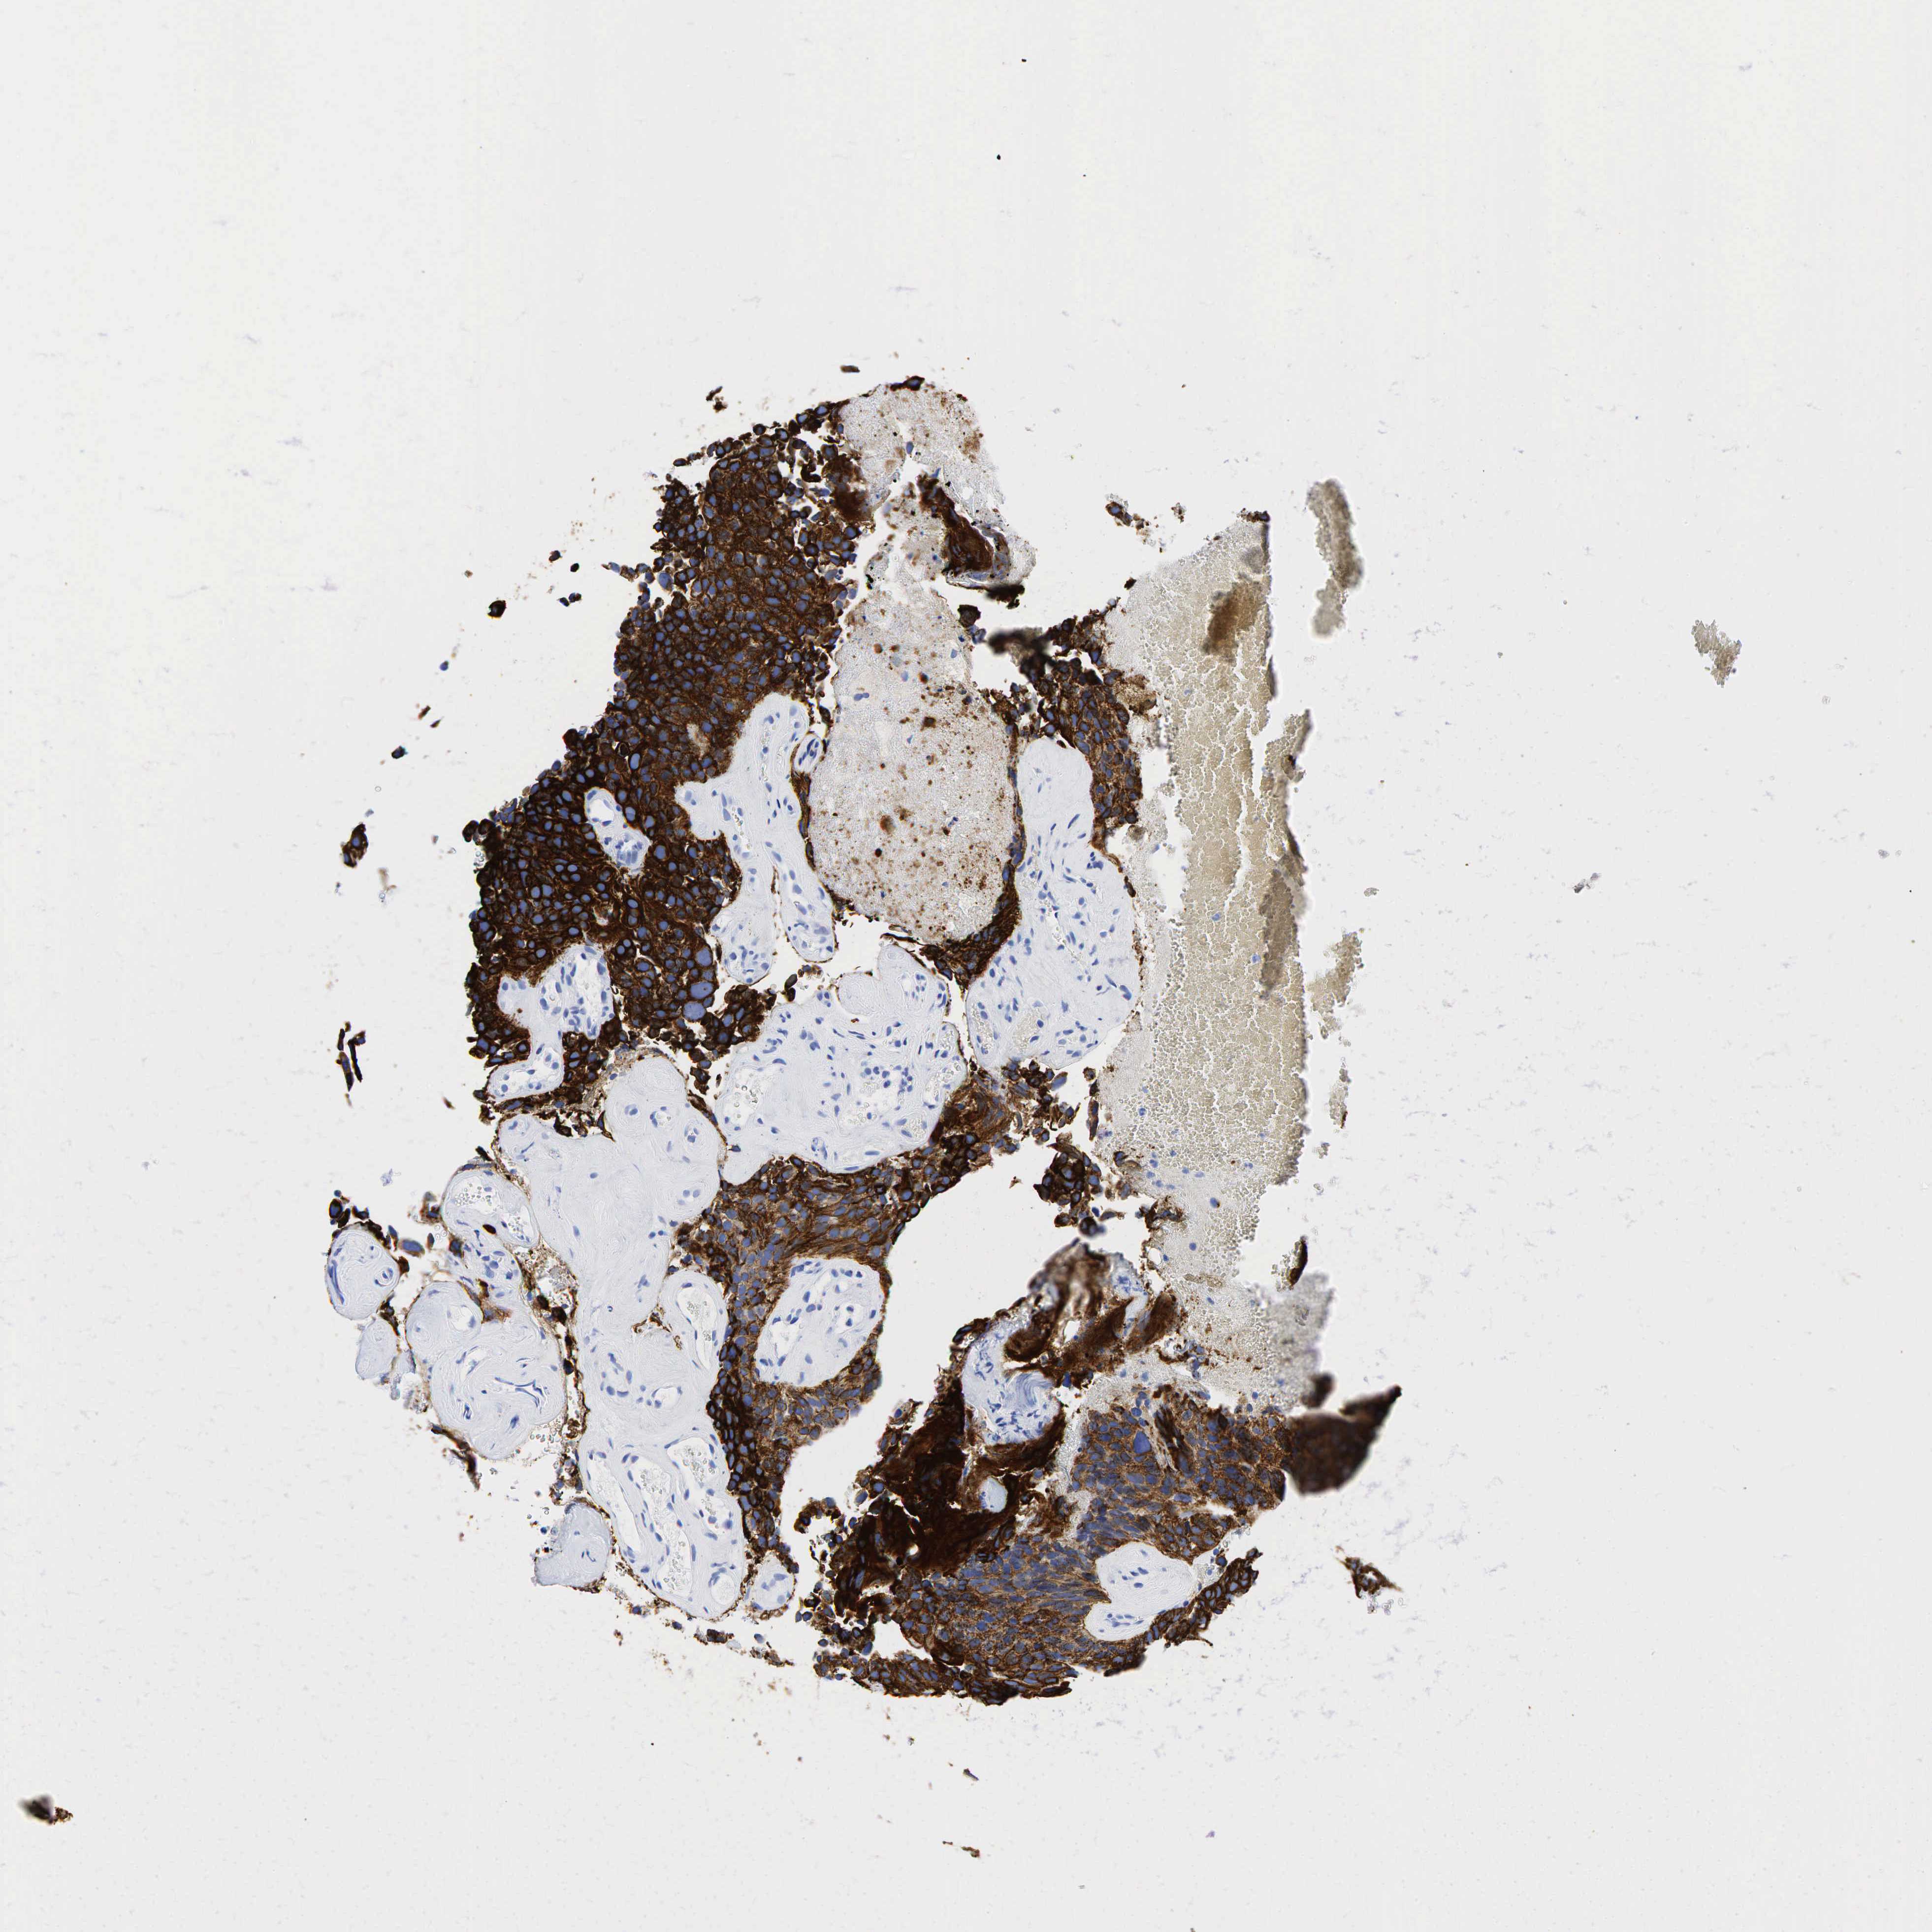

UROTHELIAL CANCER - Protein expressioni

A mouse-over function shows sample information and annotation data. Click on an image to view it in a full screen mode. Samples can be filtered based on level of antibody staining by selecting one or several of the following categories: high, medium, low and not detected. The assay and annotation is described here.

Note that samples used for immunohistochemistry by the Human Protein Atlas do not correspond to samples in the TCGA dataset.

Antibody stainingi

Antibody staining in the annotated cell types in the current human tissue is reported as not detected, low, medium, or high, based on conventional immunohistochemistry profiling in selected tissues. This score is based on the combination of the staining intensity and fraction of stained cells.

Each image is clickable and will lead to virtual microscopy that enables deeper exploration of all samples and also displays staining intensity scores, fraction scores and subcellular localization as well as patient and tissue information for each sample.

Antibody HPA002465

Antibody CAB000031

Urothelial carcinoma, High grade

Urothelial carcinoma, Low grade

Adenocarcinoma, NOS